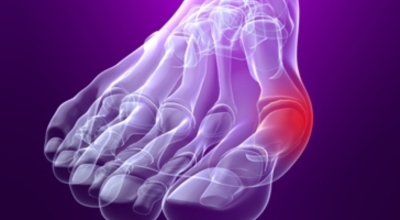

무지외반증의 증상은 뼈가 가장 많이 튀어나온 부분이 신발과 닿아서 통증이 있는 것이 일반적으로입니다. 돌출된 관절은 서 있거나 걸을 때 자극을 받아 빨개지고 바닥에도 굳은살이 발생되는 것과 같은 통증이 발생하게 되는데요 무지외반증은 진행형 특성을 갖고 있어 초기에는 발병 여부를 알지 못하다가 발에 변형이 시작되면 시간이 지날수록 통증이 악화돼요. 심하면 압박성 피부궤양을 동반하기도 합니다. 또 엄지발가락이 정상적인 기능을 하지 못하므로 비정상적인 보행을 하게 되고 이로 인해 발목이나 무릎, 허리 등에 스트레스를 줘 2차적인 질환을 불러올 수 있어요.

무지외반증은 발가락의 휘어짐 정도로 1단계 ~ 4단계까지 나눌 수 있어요.

1단계 : 15도 ~ 20도 휘어짐, 외관상 변화가 심하지 않음

2단계 : 20도 ~ 30도 휘어짐, 외관상 변화가 확연히 보임

3단계 : 30도 ~ 50도 휘어짐, 2, 3번째 발가락에 변형이 나타남

4단계 : 50도 이상 휘어짐, 정도가 심한 변형과 극심한 통증이 나타남, 정상적인 보행이 어려움

1, 2단계는 경증으로 통증이 나타나지 않으나, 3단계부터 신발을 신거나 쓸리고 눌릴 때마다 통증이 발생합니다. 4단계는 두번째 발가락이 엄지 발가락 위에 높아져 있다고 하며 뼈의 돌출이 심해진 상태라서 극심한 통증을 동반해서 신발을 신는 것 자체가 불편해지기도 합니다.